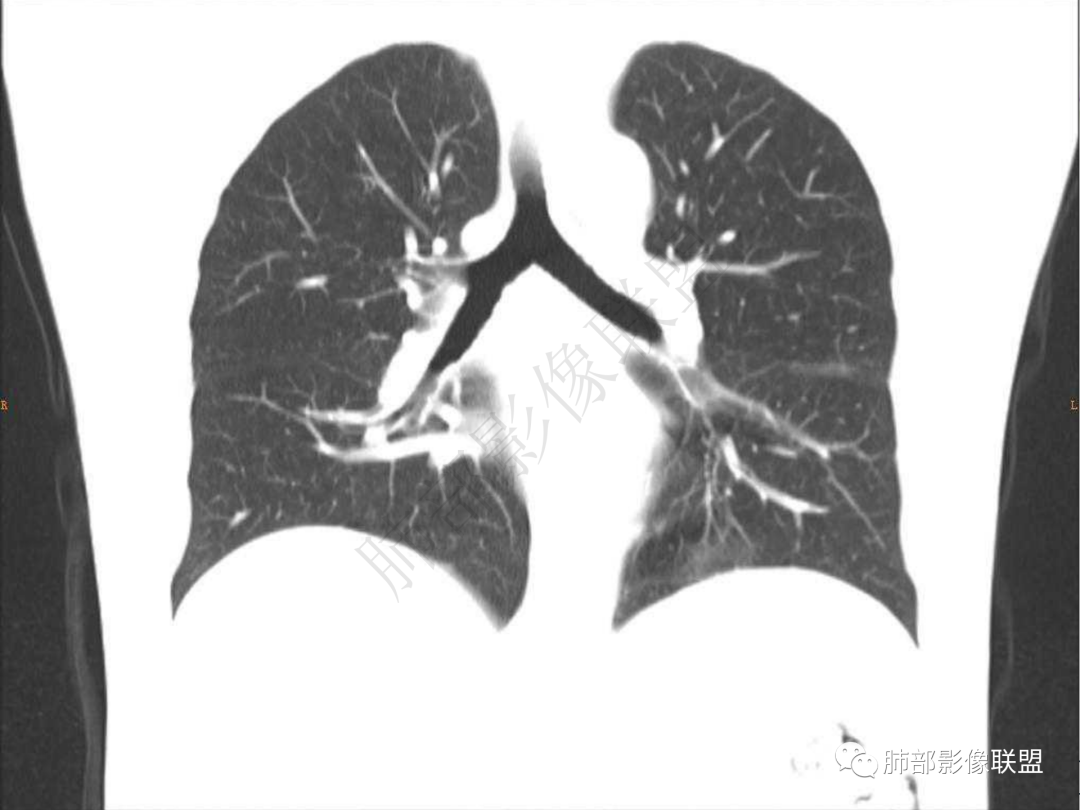

2.左肺下叶团片影,跨背段及内前基底段,实性部分类椭圆形,密度不甚均匀,可见毛刺及棘状突起,未见典型分叶及胸膜凹陷。病灶上下缘可见相应肺段支气管旁进侧出,管壁轻度增厚,未见狭窄阻塞。

3.周边较大范围磨玻璃影,边界相当模糊,小叶增厚明显。注意叶裂另一侧、左肺舌段亦可见磨玻璃影及增厚的小叶间隔。未见明确卫星病灶。

5.双肺门及纵隔未见增大淋巴结。未见胸腔积液。